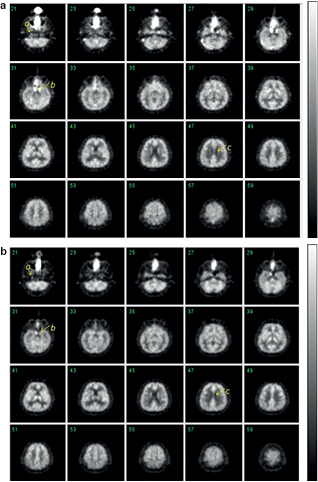

Standard image High-resolution imageFigure 8 showed the integrated transaxial PET images obtained from the healthy volunteer with the sequential inhalation protocol of 15O2 and C15O. Detailed structure of cortical grey-matter regions are reasonably visible in both relative CMRO2 and CBF images, as shown in figures 8(a) and (b), respectively. Identification of the carotid arterial lines, as well as the separation of the carotid sinus from the temporal lobe, is also well recognized. Separation of the white matter area from the cerebral spinal fluid space and the grey matter area can also be seen in these images.

Figure 8. Transaxial PET images obtained from the healthy volunteer integrated over the initial 300 s after the 15O2 inhalation (figure 8(a)) and the initial 150 s after the C15O2 inhalation (figure 8(b)). The protocol essentially followed the recently proposed dual-administration protocol on the human volunteer (Kudomi et al 2013). Arrow a indicates one of the carotid arterial lines, arrow b represents the sinus demonstrating a reasonable separation that has not been done well using previous PET scanners and arrow c demonstrates a good separation of white matter area from cerebral fluid space and cortical grey-matter regions.

In this study, we applied a standard FBP reconstruction to the 2D sinogram generated by the Fourier re-binning procedures of Defrise et al (Defrise et al 1997). Recently the point-spread function (PSF)-based reconstruction of Panin (Panin et al 2006) and/or time-of-flight (TOF) reconstruction were shown to improve image accuracy and statistical noise properties (Karp et al 2008, Lois et al 2010). Radioactivity distribution in the volunteer study demonstrated that the radioactivity distribution in the cerebellum and temporal regions were well recovered when excluding the outside-FOV correction (figure 5, 6(c)‒(f)). The integrated transverse images obtained with the 15O-oxygen and 15O-carbon dioxide inhalation demonstrated reasonable quality and the border between cerebral spinal fluid and the white matter region were clearly visible. Identification of the carotid arterial lines as well as the separation of the carotid sinus from the temporal lobe can also be clearly seen, which has been difficult when using the previous PET scanners in 2D mode. Application of PSF and TOF reconstruction may contribute to the identification of the carotid-arterial and help in noninvasively extracting the arterial input function from the time-activity curve in this area, as demonstrated by an earlier work (Iguchi et al 2013). Further studies are needed in order to evaluate the adequacy of such an approach.